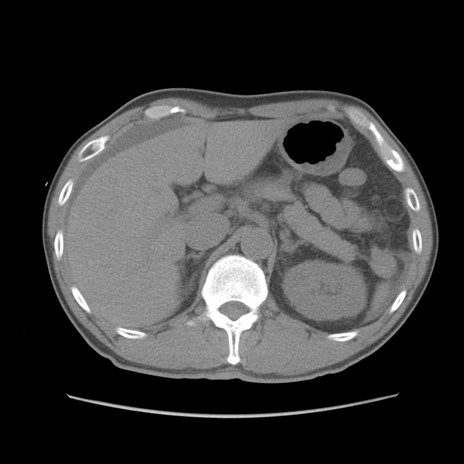

症例56 CT(横断像)

脂肪ウインドウ